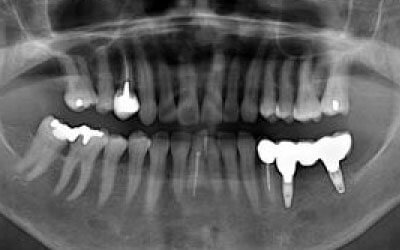

骨が薄い状態では、そのままインプラントを行うのはおすすめできません。

しかし、事前に骨を増やす処置を行ったり、インプラント埋入と同時に骨造成を行うことで、インプラント治療は十分に可能です。